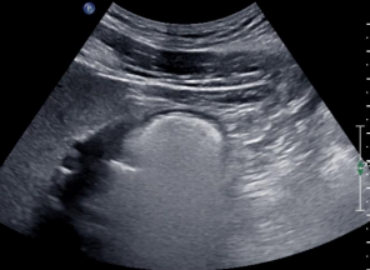

1. 胃窦为圆形或椭圆形且小而空的环状结构,形似“牛眼(图3), 宜评判为空腹。

图片

3  空腹,形似“牛眼